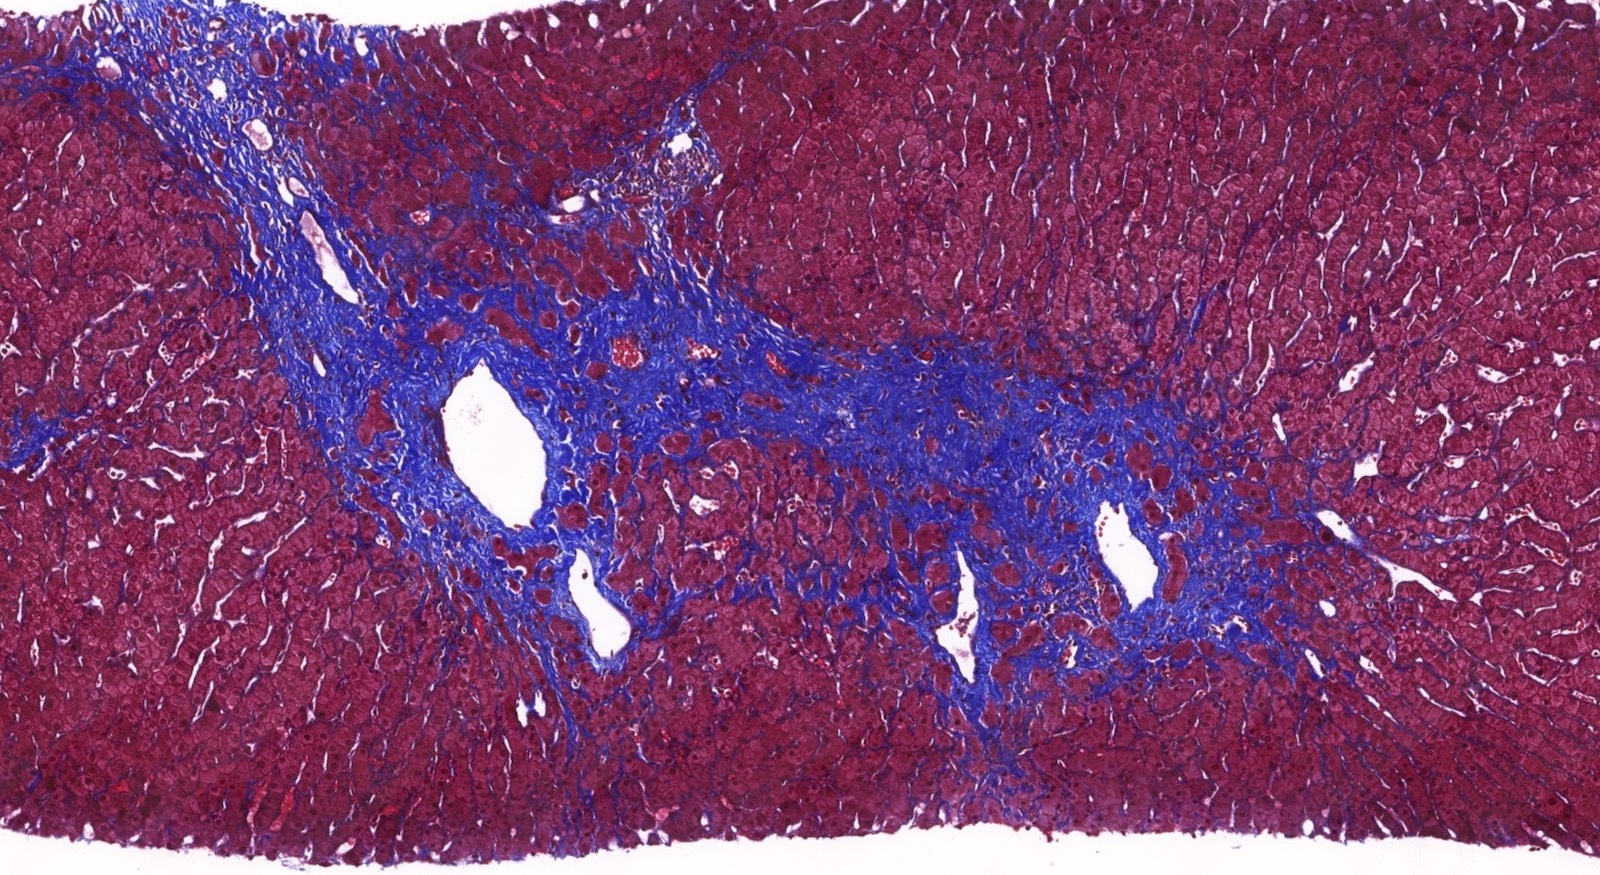

- Distinct fibrosis patterns (Am J Transplant 2016;16:603, Transplantation 2017;101:2062, Clin Transplant 2018;32:e13227, Liver Transpl 2016;22:1593, Liver Transpl 2018;24:897):

- Dense acellular portal collagen deposition: portal collagenization

- Distinct subsinusoidal and perivenular fibrosis

Microscopic (histologic) images